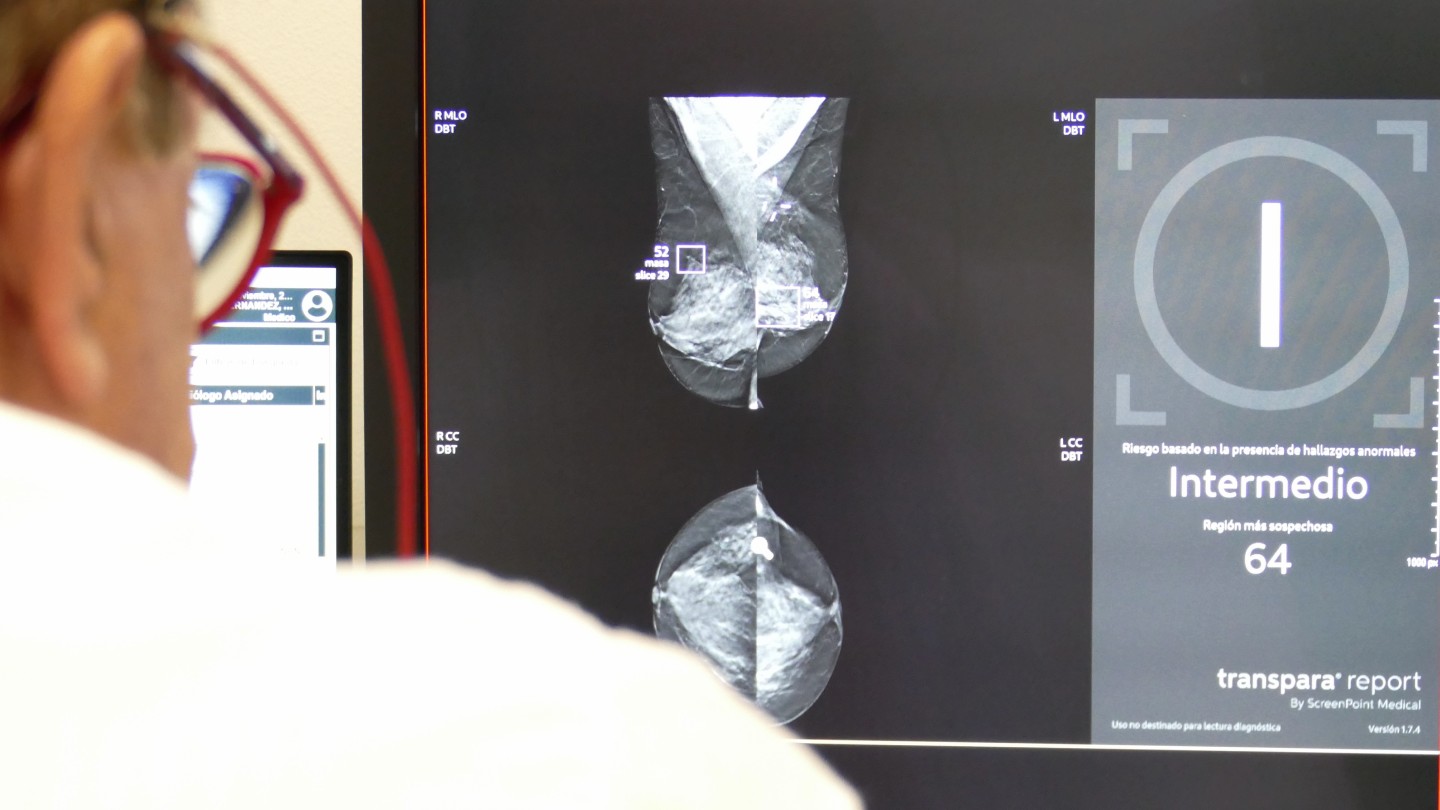

Imagen de la estadificación de riesgo de una mamografía a través de IA (mensaje a la derecha de la imagen), en la mamografía se marca la masa sospechosa encuadradas en violeta.

En el análisis mamográfico, el programa de IA analiza mamografías y ecografías, detecta lesiones sospechosas y ofrece un índice de riesgo de cáncer. "Estos análisis se realizan de forma automática. No evitan que el radiólogo deba seguir analizando la prueba, pero permiten que los más expertos puedan dedicarse solo a valorar las pruebas más complejas", explica del Dr. Martínez de Vega. "Estas IA se han entrenado analizando millones de imágenes en las que han estudiado muchas características: microcalcificaciones, densidades asimétricas, márgenes especulados… Clasifican toda esta información y nos ofrecen un análisis muy fiable".